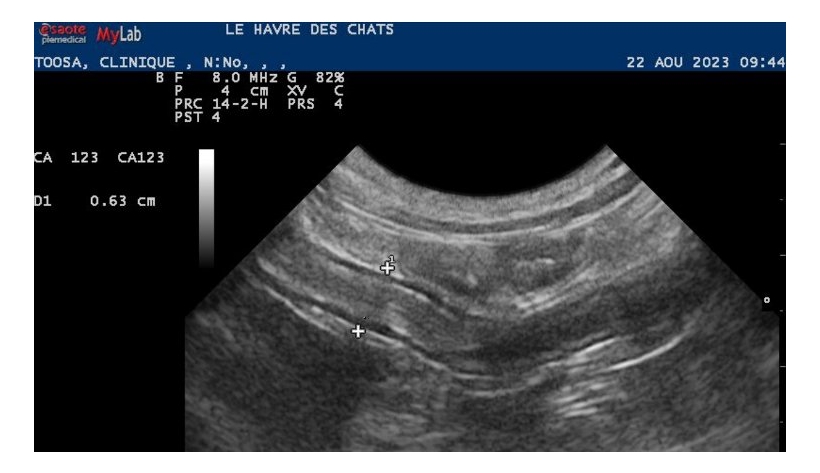

Lundi 10 Mars 2025 Animaux de compagnieFigure 5 : Epaississement de la paroi des anses intestinales en août 2023